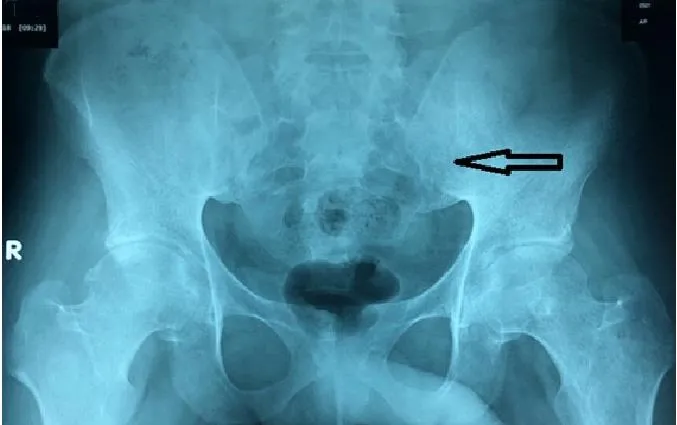

Kết quả chụp X-quang cho thấy khung chậu bệnh nhân bị tổn thương khi nhập viện. Ảnh: BV CUNG CẤP